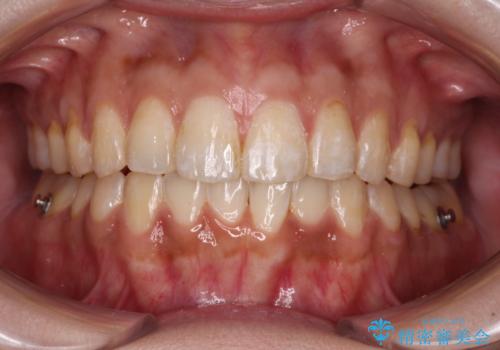

- 前歯のデコボコと上下前歯の隙間を気にして来院された患者様です。

下顎前歯はデコボコのため、歯肉が腫れやすくなっていました。

また、舌突出癖のため、上下前歯の間に隙間ができてしまい、上顎前歯が前方に傾斜している状態でした。

舌のトレーニングをしっかりと行っていただき、上下前歯をしっかりと接触させることができました。